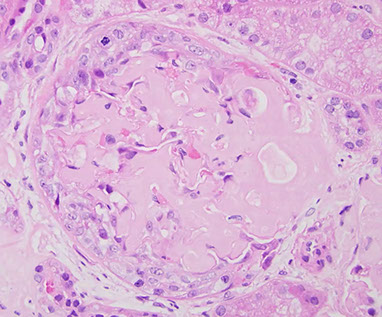

1) Ruptures in GBM make crescents by leaking leukocytes and fibrinogen into Bowman's space

2) Crescents fill Bowman's space from proliferation of epithelial cells of Bowman's capsule and macrophages and neutrophils infiltrate, eventually  causing glomerular collapse and renal failure

Histo

Must have >50% crescents

LM: crescent-moon shape (made of fibrin c plasma proteins c glomerular parietal cells, monocytes, and macrophages)